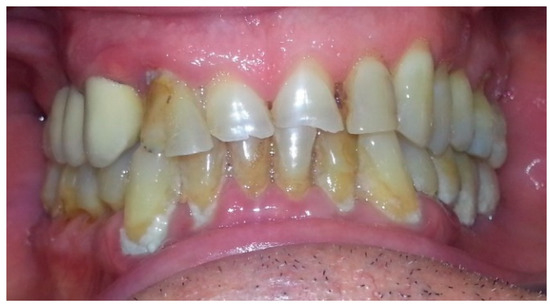

4. Case Report